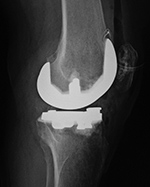

| Posterior cruciate retaining total knee arthroplasty (TKA) |

Posterior cruciate substituting total knee prosthesis and patellar resurfacing. |

| 68 year-old woman treated for severe left knee osteoarthritis |

Note the large distal femoral box. There is a surgical drain in the suprapatellar space. |